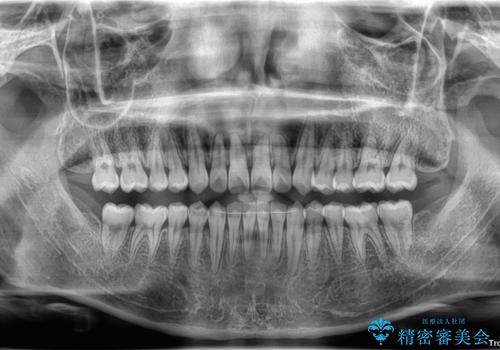

- 「前歯のすきっ歯が気になる」「食べ物が歯の間に詰まりやすい」とのお悩みで来院された20代男性の患者様です。

歯と歯の間に隙間がある**空隙歯列(すきっ歯)**は、見た目の問題だけでなく、食片圧入による歯肉の腫れや、隣接面う蝕のリスク増加につながることがあります。

診査により舌突出癖が認められました。この癖は、すきっ歯の原因となるだけでなく、矯正後の後戻りリスクを高めます。